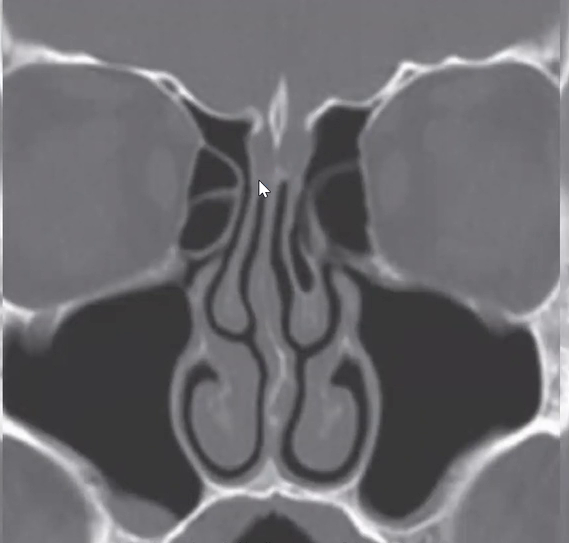

Qual a classificação de Keros da imagem?

A

Keros tipo 1 (1-3mm)